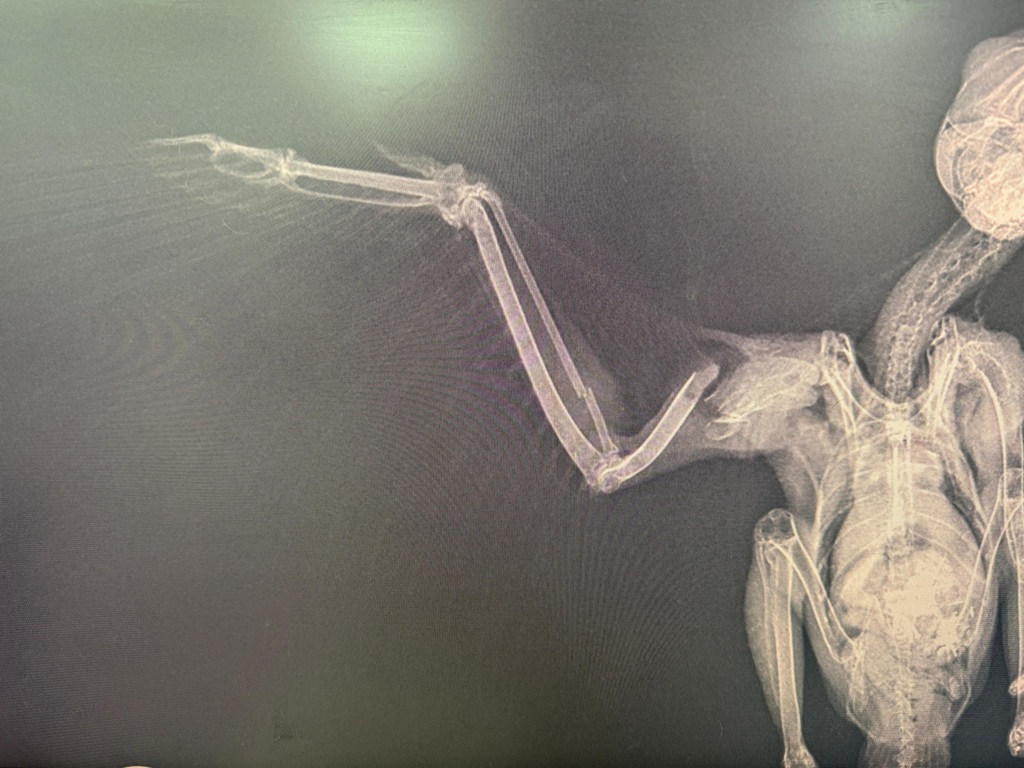

Well, that didn't take long before the next x-rays were received; this time for a kestrel which had suffered a collision on the road.

If you use the chart I put up earlier this month, you can see that there is a break in the thinner of the two central bones; this is the radius and is usually a fairly simple repair. However, on this particular bird there is also a huge open fracture higher up on the humerous. Alas these are nearly always irreparable and so with other bodily damage the bird had sustained, we had to make the sad decision it was kindest to put the bird to sleep. With kestrels especially, they need to be able to hover in order to hunt, and thus need a perfect set of wings, whereas the majority of other birds such as a pigeon, corvid, gull or songbird can manage very well with a slightly dropped wing and just adapt their method of flight to suit.